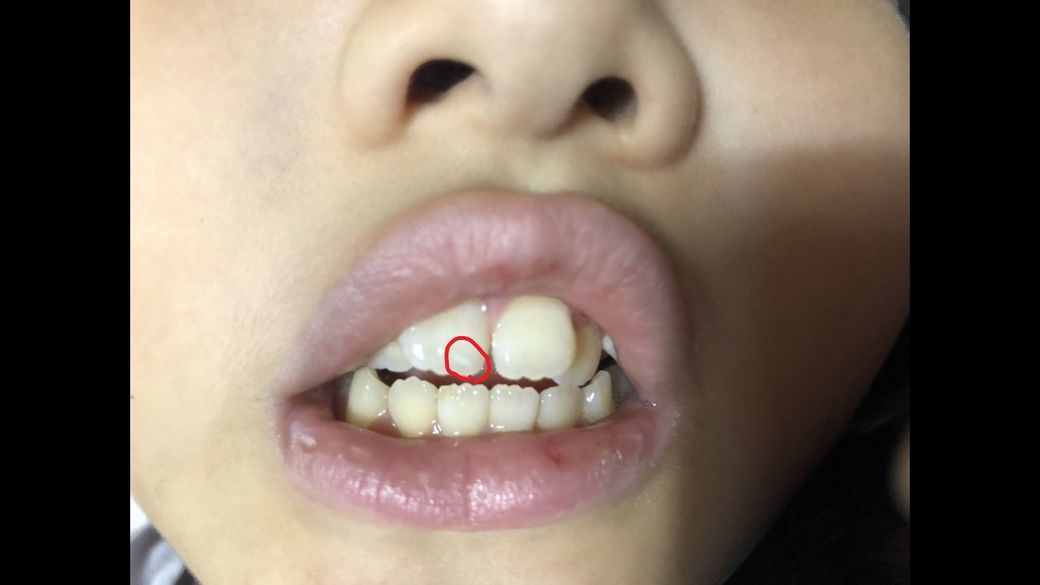

아이 앞니 치아끝이 흰색으로 변색이 되었습니다. 그전에는 자세히 보지않아서 기억은 안나는데 정상이였던거 같구요.

어제 오전에 살짝 작은 부분만 흰색이였는데 오늘보니 앞니 아랫니 끝이 다 흰색으로 색이 변했습니다.

9월 10일 좀전에 치아를 다시 확인해보니 저렇게 변해있었습니다. 하루 사이에 치아색이 이렇게 변할 수 있나요? 아니면 어제도 제가 제대로 못본건지ㅜㅜ 치아 표면은 매끄러운거 같고 손톱으로 긁었을때 굴곡이 있는거나 깨진거 같지는 않은데 하얀 색이 커져서 너무 놀라서 질문 드립니다.ㅜㅜ아이가 아프다는 말은 따로 없었습니다. 휴일이고 치과를 가려면 화요일은 되야할거 같아서요.

외상이 있었는지도 정확하지도 않지만 (제발 아니길 바라며) 혹시나 외상으로 치아가 하얗게 변하기도 하나요? 아니면 다른이유로 저렇게 하루아침에 치아가 변색되기도 하는건가요? 걱정이되서 이렇게라도 질문 드립니다.

일반적으로 하얀색 점같은 경우는 치아가 탈회된 상태로 볼수 있습니다. 외상에 의해서 생긴거 같진 않지만, 아이가 탄산이나 음료를 자주 마시는게 아닌지 의심이 되네요. 일반적으로 저러 하얀점은 아이의 식습관에 의해서 생기게 됩니다. 치아 수분에 따라서 흰색부위가 더 잘보이거나 안보일수는 잇을것같습니다.

현재 말씀하신 부위는 외상에 의해서 나타난 것이 아닌 초기충치가 이어져서 치아가 파절된 것으로 보입니다. 원래 해당 부위에는 치아가 투명색으로 보이나 치아가 충치로 인하여 파절되어 뒷 부분이 비춰서 검정색으로 보이는 것입니다. 저 정도를 외상으로 발생하려면 이미 연조직에도 손상이 나타나야 하는데 연조직 손상은 없는 것으로 보아 충치일 가능성이 큽니다. 초기 충치 패턴과 매우 유사합니다.

치아탈회일 가능성이 있습니다.

치아 탈회는 치아 표면이 조금씩 하얗게 변하며 부식되는 질환 입니다.

원인은 불소성분의 침착. 치태관리 미흡 등이 있습니다.

치아탈회는 완성된 형태의 충치가 아니므로 잘 관리하면 충치로 진행을 막을수 있습니다.